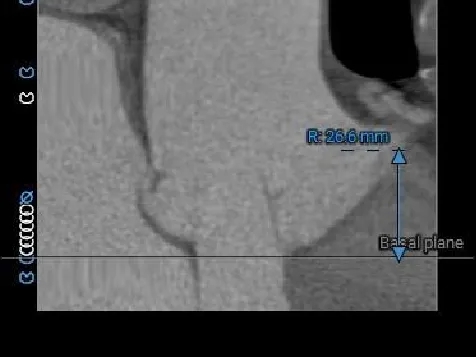

LCA Height

RCA Height

LCA & Leaflet

RCA & Leaflet

冠脉开口高度可,瓣叶不长,冠脉阻挡风险不高